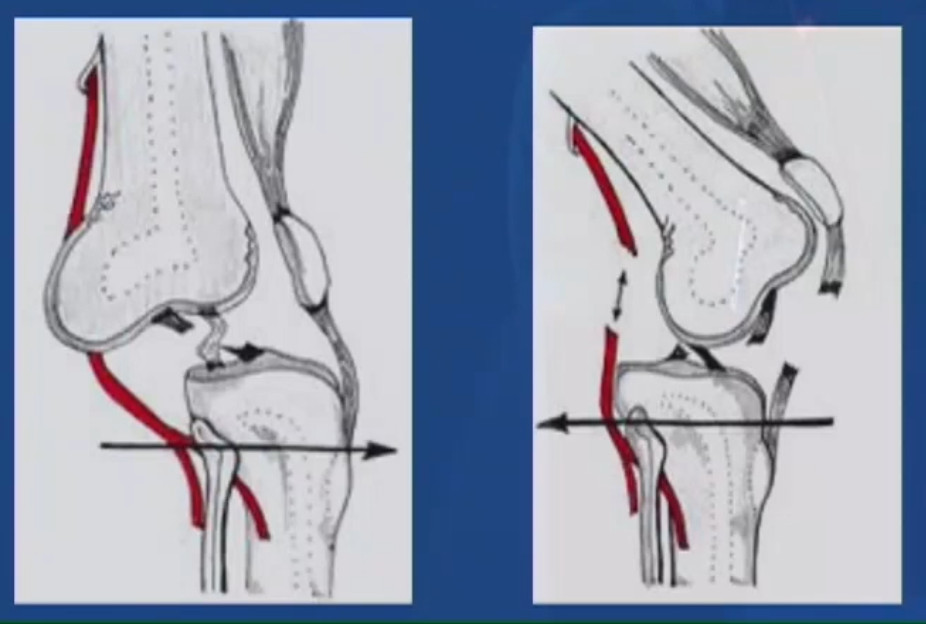

Варианты перелома надколенникаЧаще всего встречаются горизонтальные переломы. Так как к верхней части надколенника крепится сухожилие четырехглавой мышцы, которая тянет надколенник вверх, то, как правило, костные отломки разобщаются и между ними появляется щель. Такой перелом уже называется переломом со смещением.

Как мы уже отмечали, может произойти и отрыв нижнего края надколенника. При таком варианте линия перелома проходит в самом низу надколенника, там, где на его внутренней поверхности уже нет хряща.

Переломы надколенника возникают от непосредственного удара по надколеннику, от сильного и быстрого сокращения четырехглавой мышцы бедра или одновременного действия этих двух моментов. Наиболее часты поперечные переломы (линия перелома делит надколенник на верхнюю и нижнюю части). Встречаются также переломы нижнего полюса надколенника и его краев (маргинальные переломы). Вертикальные переломы встречаются редко и иногда не диагностируются.

Другие повреждения системы экстензора: Любая травма системы экстензора с рентгенографическим исследованием, исключающая перелом коленной чашечки, должна вызвать разрыв разгибательной системы: сухожилие надколенника, квадратичное сухожилие или разрыв сухожилия надколенника на передней многолицевой бугристости.

Этиология и эпидемиология

Из-за подкожного переднего расположения, биомеханической функции и высокого уровня передачи силы во время разгибания и сгибания стабильная реконструкция переломов надколенника по-прежнему представляет собой серьезную хирургическую проблему. Большинство случаев вызвано механизмом прямого повреждения [65]. Получающийся в результате тип перелома зависит от механизма травмы (т.е. прямой или косвенный), энергии, передаваемой кость, и качества кости.Наиболее распространенная модель перелома — это простое отклонение от двух частей, вызванное прямым ударом (например, травмой приборной панели). В результате костного поражения разгибательный механизм коленного сустава может стать недостаточным. Степень недостаточности зависит, среди прочего, от сопутствующего повреждения резервных разгибательных механизмов. Дополнительные травмы соседних костей встречаются редко, но могут поражать суставную поверхность дистального отдела бедренной кости. Наиболее частый косвенный механизм — это падение на ступни с эксцентрическим сокращением четырехглавой мышцы. В зависимости от скорости падения и сопротивления разгибающего механизма надколенник или прилегающие сухожилия выходят из строя [75].